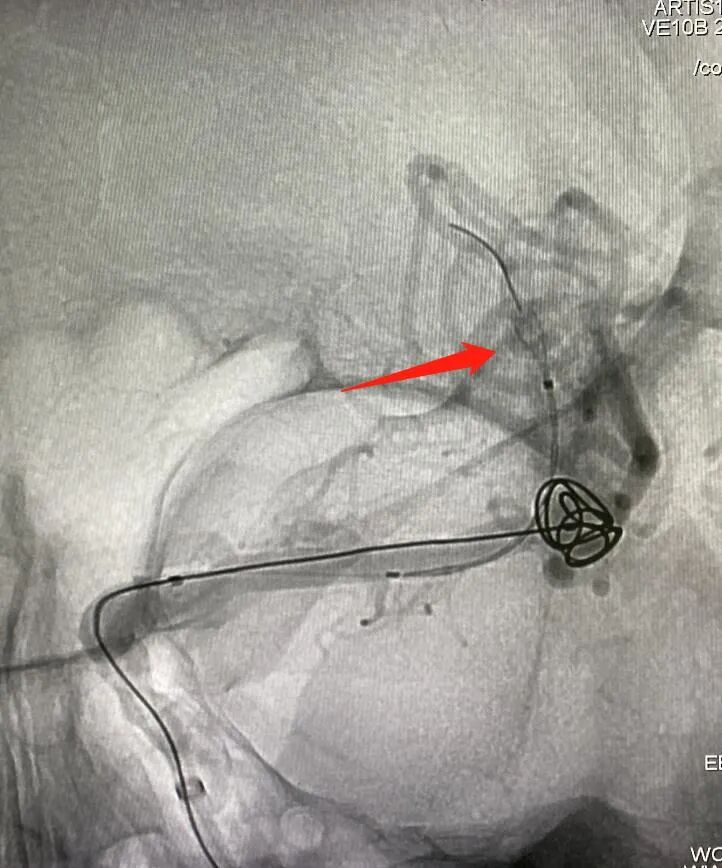

超选MCA上干血管,将Accessway支架微导管置入载瘤动脉远端。

调整畅医达(Choydar)FD(2.5×20mm)至合适位置,瘤体内填入少量弹簧圈后支架半释放。

畅医达(Choydar)血流导向装置完全释放。

术后即刻造影提示载瘤动脉通畅,支架打开充分,贴壁良好,瘤体内造影剂滞留明显。